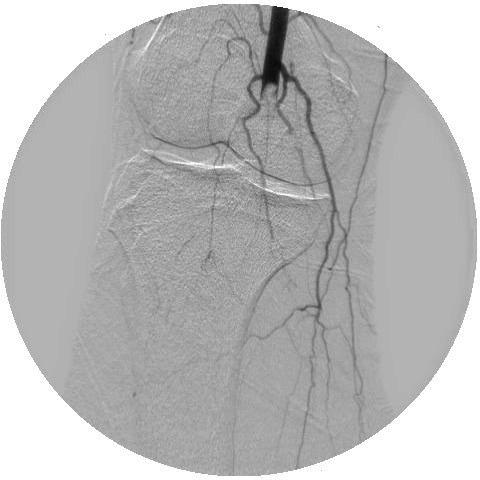

COVID-19 is caused by the SARS-CoV-2, and its presentation ranges from mild upper respiratory illness to critical disease including acute respiratory distress syndrome and multiorgan dysfunction. While it was initially believed to primarily target the respiratory system, numerous studies have demonstrated it to cause a hypercoagulable state that predisposes to arterial and venous thrombosis. We present a case where a patient with COVID-19 developed acute lower limb ischaemia due to arterial thrombosis in the setting of full-dose enoxaparin, followed by heparin infusion protocol. The patient developed recurrent ischaemia despite thrombolysis in addition to anticoagulation, and eventually required open thrombectomy before making a full recovery.

COVID-19 由 SARS-CoV-2 引起,其表现从轻症上呼吸道疾病到包括急性呼吸窘迫综合征和多器官功能障碍在内的重症不等。虽然最初认为它主要针对呼吸系统,但许多研究表明它会导致高凝状态,从而容易发生动脉和静脉血栓形成。我们提出了一个病例,一名 COVID-19 患者在接受全剂量依诺肝素的情况下发生了动脉血栓形成导致急性下肢缺血,随后开始肝素输注方案。尽管进行了溶栓和抗凝治疗,但患者仍反复发生缺血,最终需要进行开放血栓切除术才能完全康复。